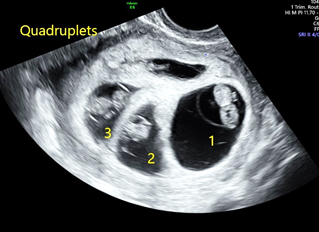

A multiple pregnancy is one in which the mother carries more than one baby in her womb. Most commonly is it two called as twins. If there are three, it is called as triplet and if four, it is quadruplet pregnancy..

• Early viability scan- this scan is to determine the number of fetuses and type of multiple pregnancy, that is to determine the CHORIONICITY.

• First trimester screening- at 11-13+6weeks- Here, we determine the number of fetuses, type of multiple pregnancy, dating, structural abnormalities and screen for chromosomal abnormalities.